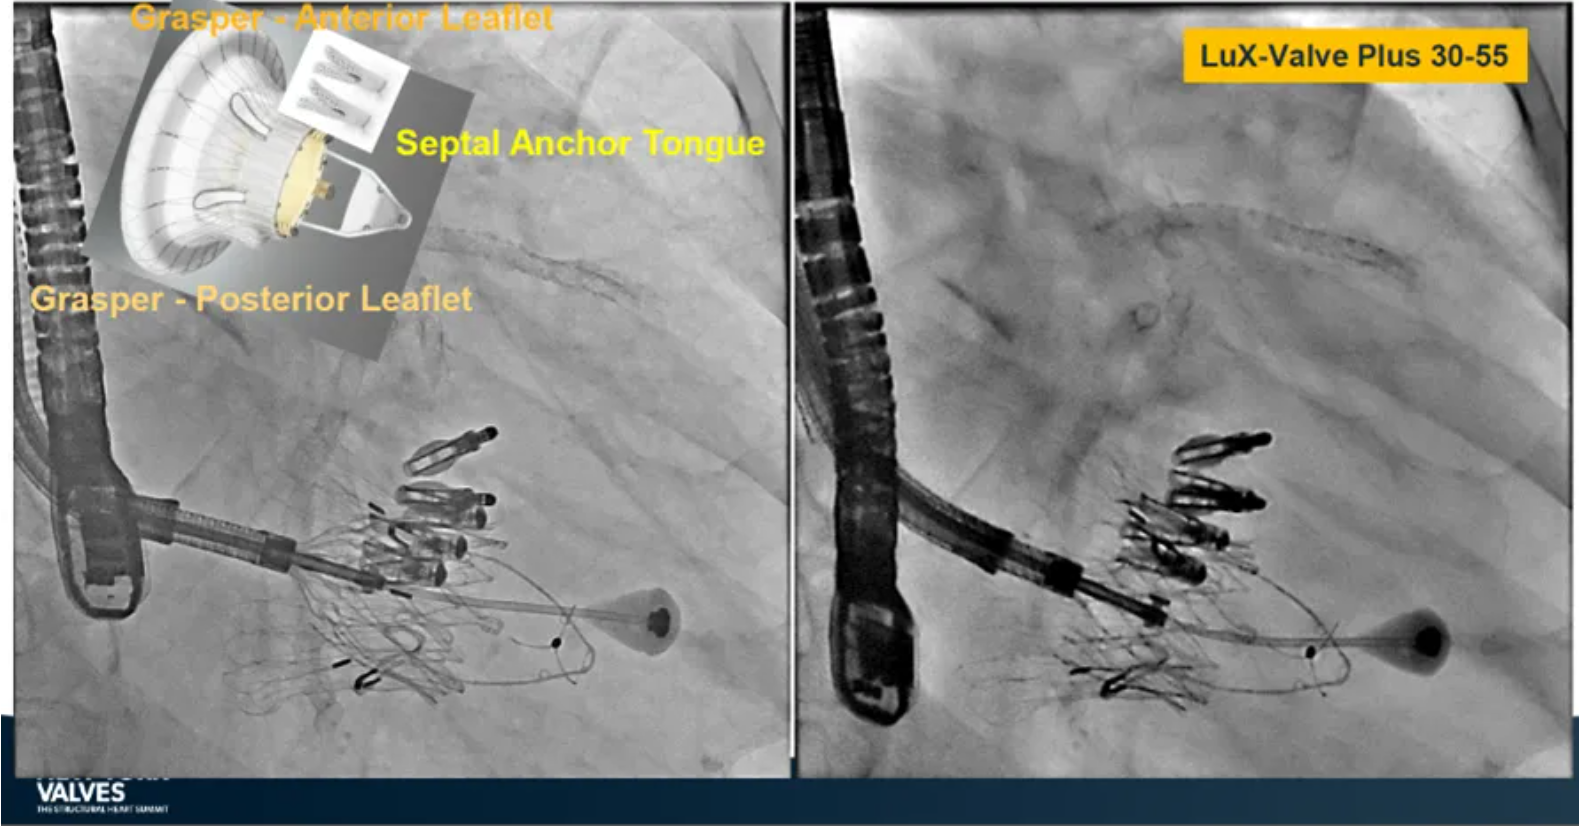

Granada教授表示,LuX-Valve Plus是一款不依賴于徑向支撐力固定的多功能TTVR器械,它的創(chuàng)新設(shè)計(jì)(室間隔錨定和瓣葉夾持件)提供了多樣的固定和穩(wěn)定技術(shù)。多中心臨床試驗(yàn)研究TRAVEL II 展現(xiàn)了LuX-Valve Plus的安全性和有效性,能實(shí)現(xiàn)較短的器械操作時(shí)間,較低的復(fù)合事件發(fā)生率,并在6個(gè)月期時(shí)顯著降低三尖瓣反流等級(jí),以及帶來(lái)心功能和生活質(zhì)量等指標(biāo)上的明顯改善。

來(lái)自法國(guó)波爾多大學(xué)醫(yī)院(CHU de Bordeaux, Bordeaux, France)的Thomas Modine教授在2024紐約瓣膜會(huì)上介紹到針對(duì)目前三尖瓣反流臨床上的痛點(diǎn),包括大瓣環(huán)、起搏器或者心臟除顫器ICD導(dǎo)線的影響、依賴術(shù)中影像,以及術(shù)后起搏器的植入等,LuX-Valve Plus都能夠提供良好的解決方案。他在最后總結(jié)道,LuX-Valve Plus創(chuàng)新的設(shè)計(jì)能夠有效降低術(shù)后的并發(fā)癥,例如起搏器植入率和血栓的形成。同時(shí),TRAVEL II 研究的6個(gè)月期數(shù)據(jù)也體現(xiàn)了產(chǎn)品較短的器械操作時(shí)間,較低的復(fù)合事件發(fā)生率,顯著改善的心功能和生活質(zhì)量,以及能夠跟術(shù)前就已經(jīng)存在的起搏器導(dǎo)線兼容的優(yōu)勢(shì)。

來(lái)自中國(guó)香港瑪麗醫(yī)院(Queen Mary Hospital, Hong Kong, China)的Simon Lam教授在2024紐約瓣膜會(huì)上分享了一例復(fù)雜案例,一名高齡男性患者在2年前行二尖瓣和三尖瓣TEER術(shù)式后繼發(fā)三尖瓣反流,遂再次行二尖瓣TEER術(shù)式和用LuX-Valve Plus行三尖瓣TTVR術(shù)式。

本次術(shù)式中,LuX-Valve Plus的植入緊隨二尖瓣修復(fù)術(shù)式之后,且并未取出前期植入的三尖瓣修復(fù)夾,這意味著LuX-Valve Plus在患者有過(guò)二尖瓣和三尖瓣修復(fù)夾植入情況下的兼容性,并且?guī)?lái)了有效的治療結(jié)果。此外,這不僅體現(xiàn)了LuX-Valve Plus可以與二尖瓣術(shù)式并行,更可以兼容三尖瓣原位的其他修復(fù)夾產(chǎn)品。

來(lái)自中國(guó)上海復(fù)旦大學(xué)附屬中山醫(yī)院的魏來(lái)教授在2024年臺(tái)北瓣膜高峰論壇上分享了他使用LuX-Valve Plus治療三尖瓣反流的經(jīng)驗(yàn)。魏來(lái)教授闡述道,隨著療法演變,目前全球市場(chǎng)有以LuX-Valve Plus及其他產(chǎn)品為代表的經(jīng)導(dǎo)管三尖瓣介入置換系統(tǒng),逐漸成為重度三尖瓣反流的一線治療方案。他介紹到,LuX-Valve Plus創(chuàng)新的室間隔錨定和經(jīng)頸靜脈入路的方式,能夠帶來(lái)安全穩(wěn)定的錨定效果及較短的輸送行程;其可調(diào)彎的輸送系統(tǒng)能保證同軸性,從而快速和安全地將人工瓣膜送達(dá)目標(biāo)手術(shù)區(qū)域,有效降低入路周邊解剖組織并發(fā)癥及術(shù)中出血風(fēng)險(xiǎn)。